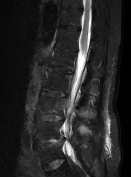

收治入院后感染科积极安排超声引导下腰背部软组织积液穿刺,抽出淡红色液体0.5ml,细菌培养提示金黄色葡萄球菌。经过2个月的针对性抗感染治疗,张奶奶的腰痛症状逐渐好转,从最开始的翻身困难、下肢抽痛,到行走自如。期间动态复查腰椎核磁,可见脓肿逐渐吸收,出院后3个月张奶奶再次来复查,脓肿已完全吸收,张奶奶的生活回到正轨!

治疗5周

出院后3个月